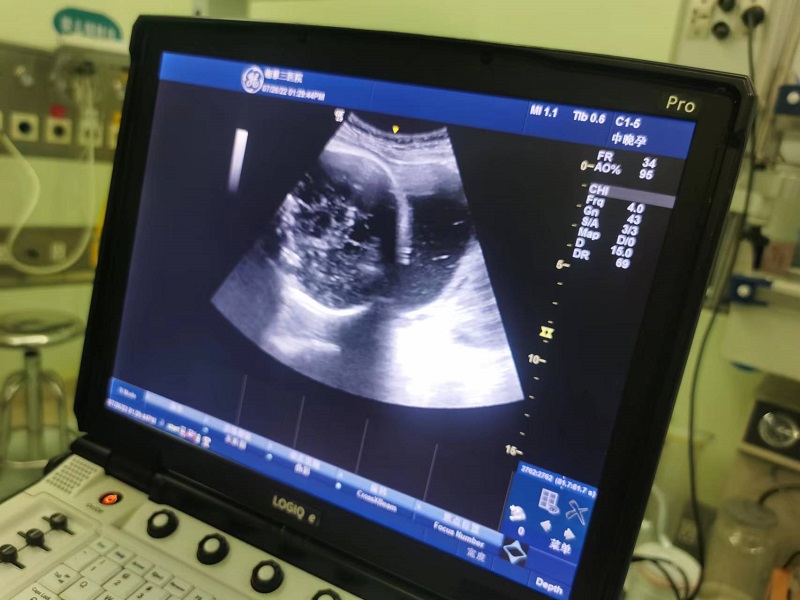

图片2:术后B超提示头位

据了解,孕妇为29岁经产妇,G2P1宫内妊娠37周4天,臀位,有强烈阴道分娩诉求,但对臀位阴道分娩并发症很担忧,遂至产科要求行臀位外倒转术。术中超声实时监测胎位及胎心,术后无腹痛、阴道流血、流液等不适,胎心监护一切正常,超声确定胎位为头位(LOT)。